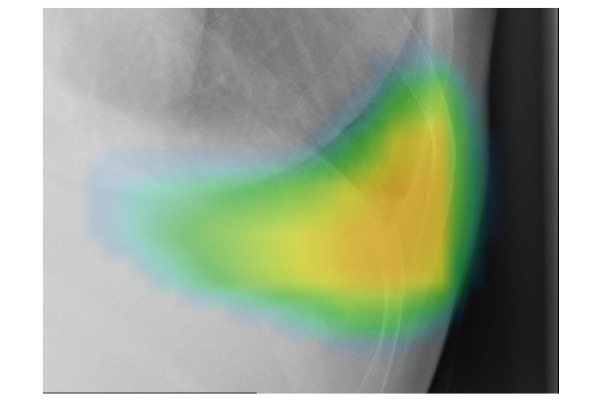

CXR-AIDが候補領域の解析をおこなったのち、0~100に応じた確信度を色分けして表示。

ヒートマップと輪郭の表示は3パターンから選択可能です。